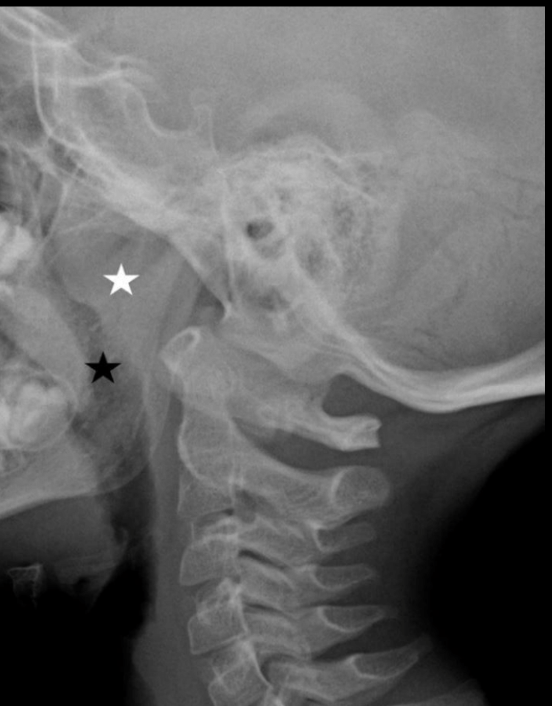

Q

¿Qué señalan las estrellas?

A

Blanca - engrosamiento de adenides

Negra - estenosis de columna aérea